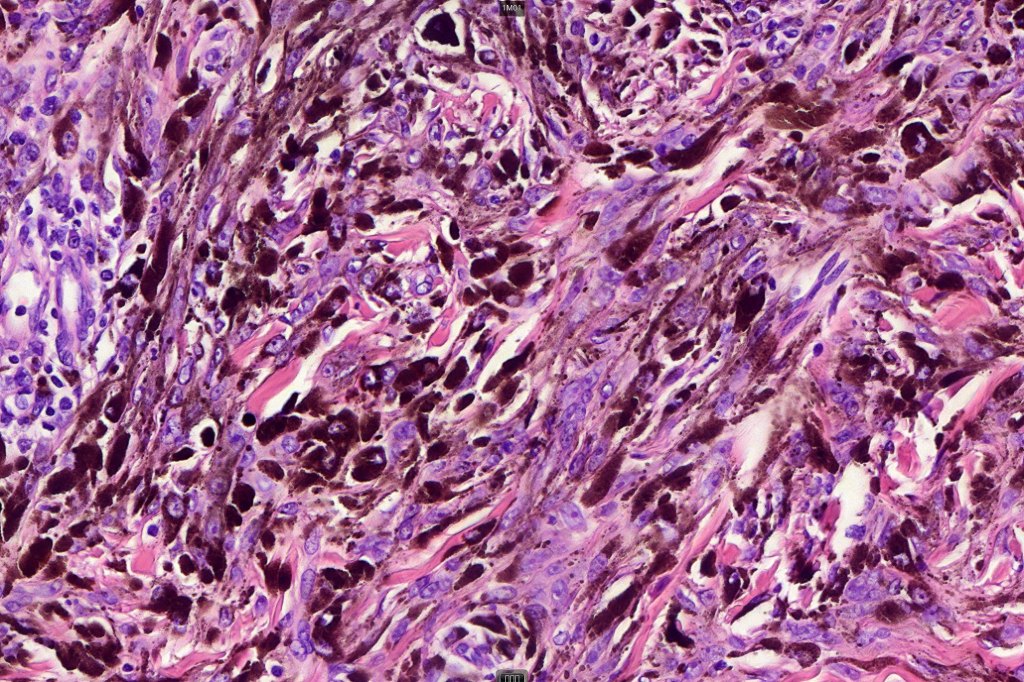

•Composed of an admixture of large epithelioid melanocytes with vesicular nuclei containing a very prominent nucleolus (fried egg cells), spindle cells, dendritic cells & melanophages

•The epithelioid cells are typically very uniform

•Few mitoses

•Perineural infiltration sometimes evident

•Absent necrosis & lymphovascular invasion